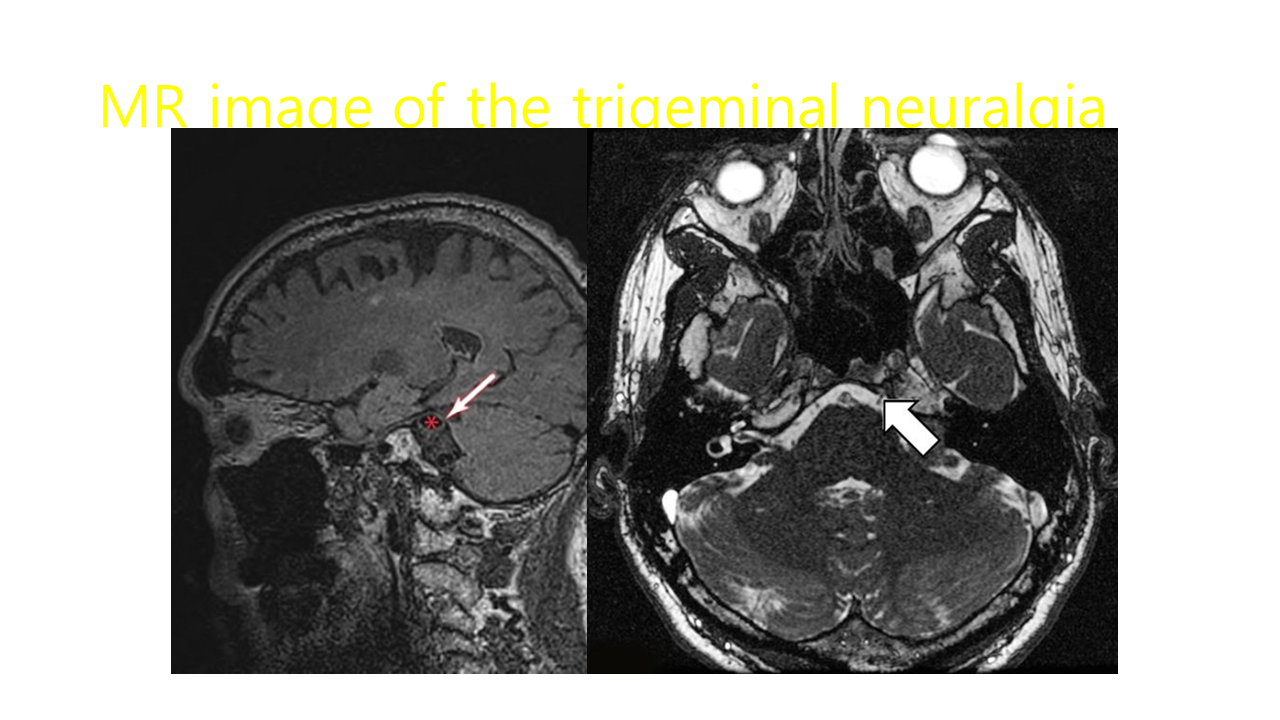

삼차신경통은 50~60대에 흔히 발생하며 여성이 남성보다 6:4 정도로 발생빈도가 높습니다.

삼차신경 분포 영역에서 대개 편측성으로 나타나 수 초 또는 수 분간 지속되는 찌르는 듯한 양상

의 재발성 통증이 특징입니다.

삼차신경통의 통증은 얼굴을 만지거나, 면도, 대화, 양치 등과 같은 비통증성 자극에 의해 나타나며 발통대(trigger zone)가 존재할 수 있습니다.

삼차신경통은 삼차신경의 하나 이상의 분지에 나타나며 주로 삼차신경의 상악 분지 및 하악 분지에 많이 나타나고 안분지에 나타나 는 경우는 흔하지 않습니다. 분지별 발생 빈도는 상악분지, 하악분지, 안분지 순이며 안분지에서 발생하

는 경우는 4~7%로 가장 드물다고 알려져 있습니다.